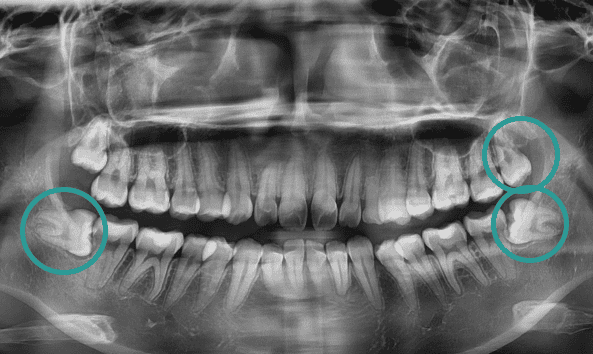

골치 아픈 사랑니, 대학병원 가지 않으셔도 됩니다.

사랑니는 기형적으로 맹출되거나

잇몸 속에 매복되는 경우가 많아 발치가 까다로울 수 있습니다.

특히, 인접 치아를 손상시키지 않고 신경을 보호하며 발치하려면

전문적인 노하우가 필수입니다. 그래서 사랑니 발치는 많은 고민과 망설임을 동반하는

어려운 선택이 될 수 있습니다. 올디플란트치과는 이런 걱정을 덜어드릴 자신이 있습니다.

사랑니 발치를 위해 치과를 찾아 헤매고 계신가요?

매복 사랑니는 신경과 가까워 발치 시

신경 손상의 위험이 높아

일부 동네 치과에서는 치료를 권하지 않기도 합니다.

하지만 올디플란트치과는

대학병원 가기 전에 방문하는 치과로 유명하며,

타원에서 발치하지 못한 케이스도

책임지고 해결해드리고 있습니다.